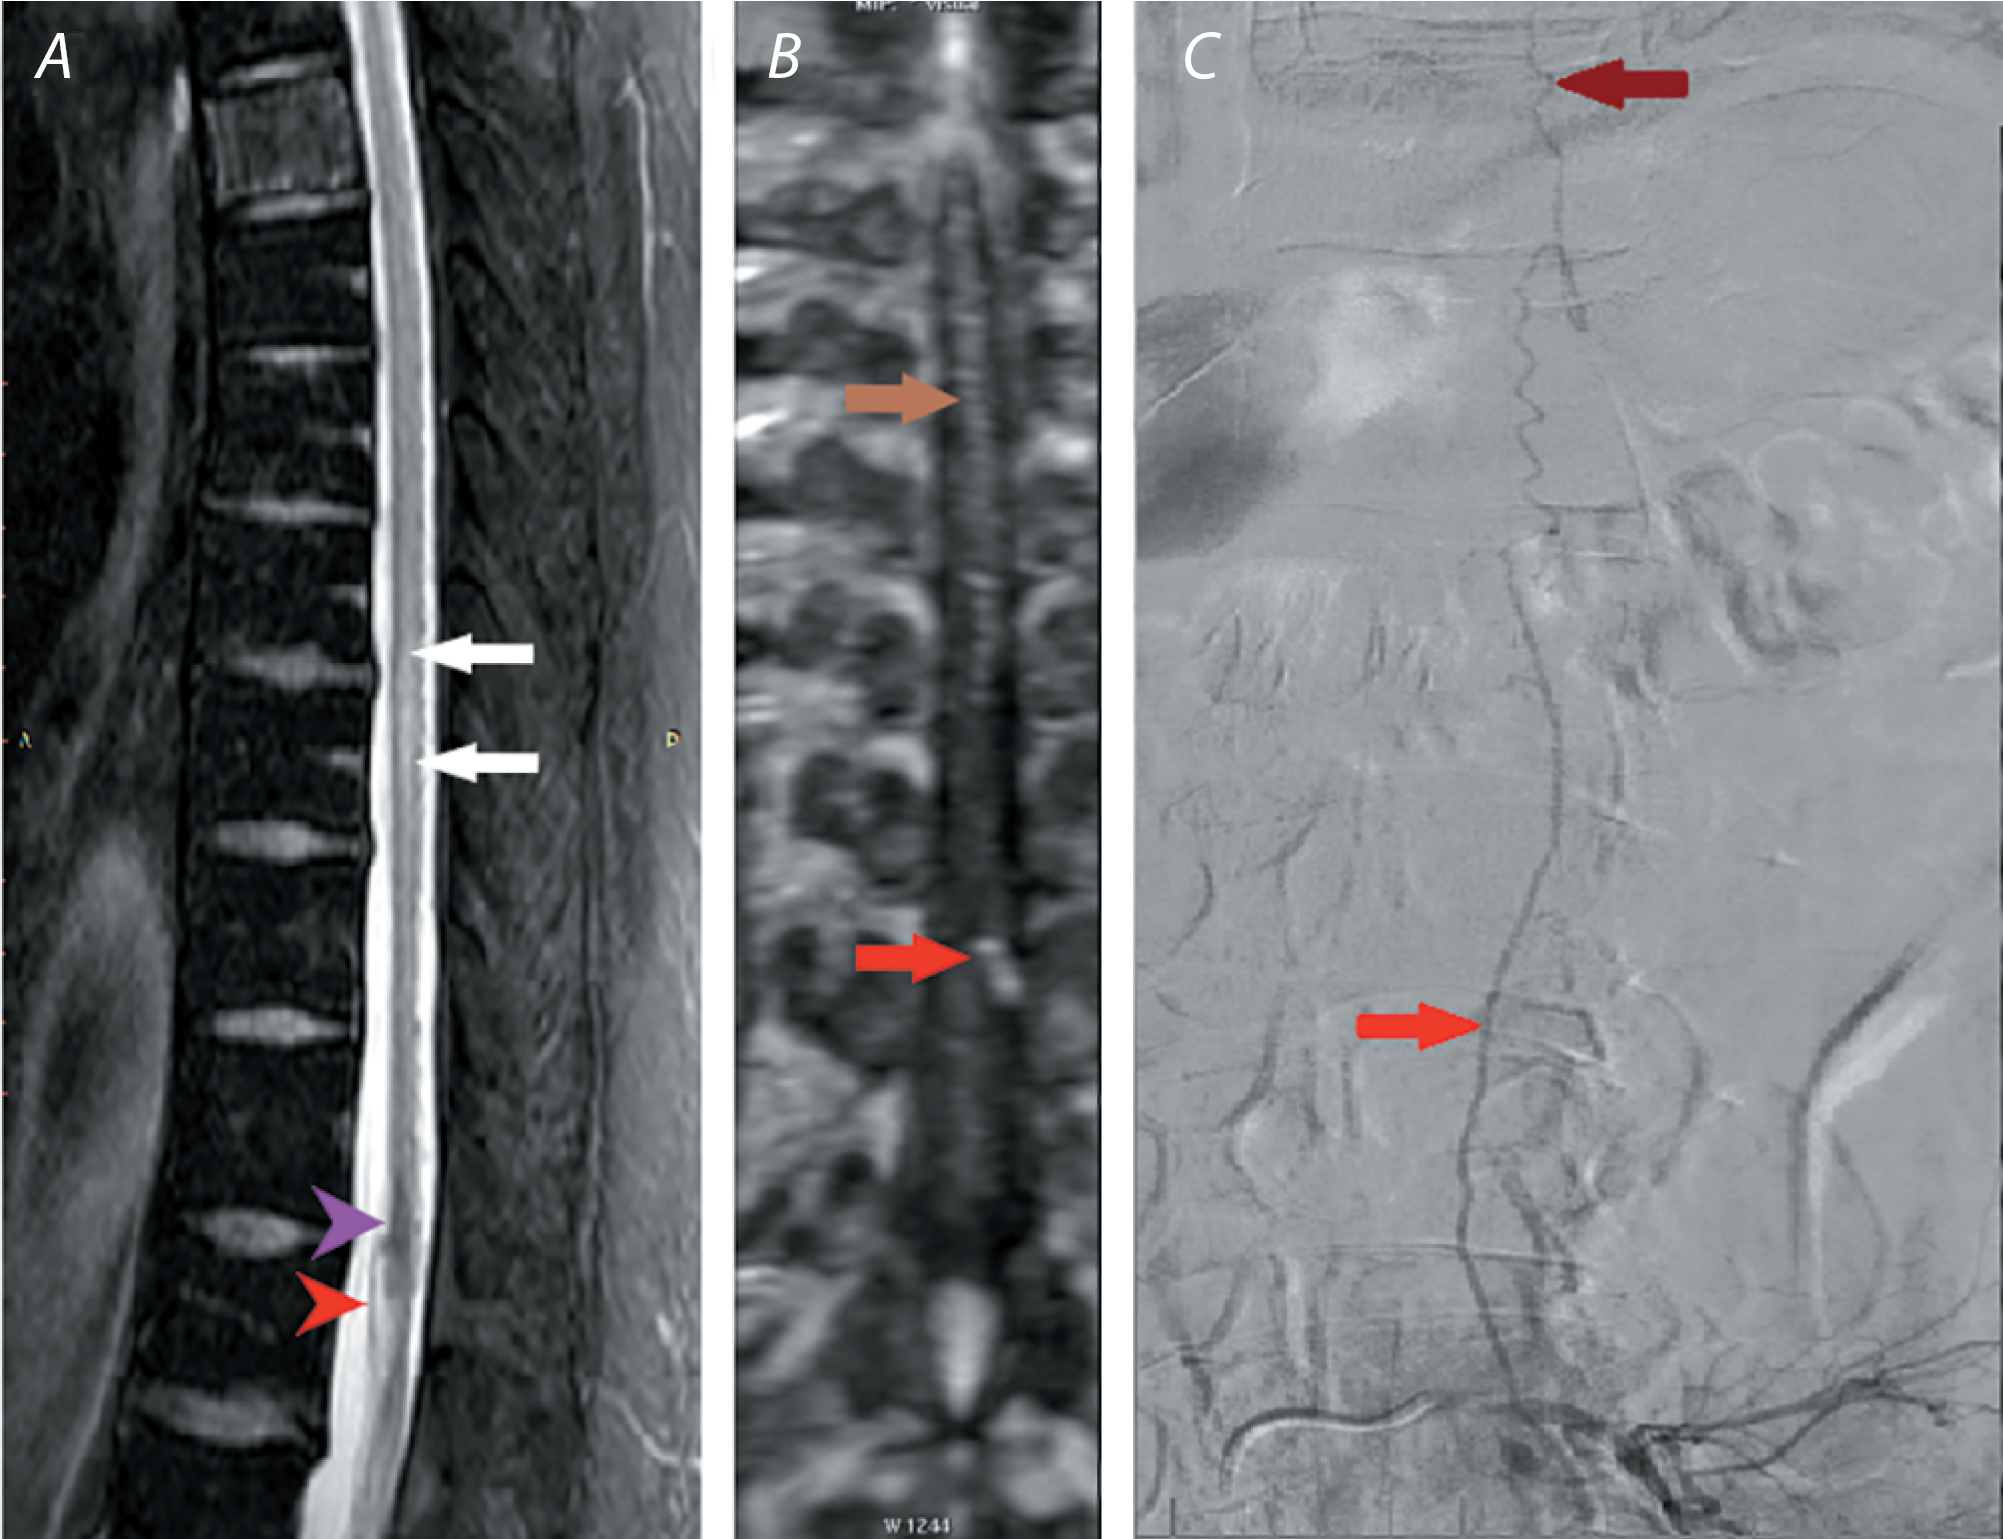

МР-проявления СДАВФ отражают патофизиологическую картину венозной гипертензии: главными признаками являются отёк нижнегрудных и каудальных сегментов СМ с гиперинтенсивностью на Т2-ВИ и гипоинтенсивностью на Т1-ВИ и извитость расширенных перимедуллярных вен СМ, располагающихся, как правило, на его дорсальной поверхности. Эти извитые вены проявляются в виде линейных областей «пустоты потока» на Т2-ВИ или накапливающих контрастное вещество структур на постконтрастных Т1-ВИ (рис. 3). В случае выраженного отёка СМ вены могут не визуализироваться вследствие масс-эффекта [40]. Также могут определяться ограниченные, часто чётко очерченные образования с гипоинтенсивным ободком, обусловленным отложениями гемосидерина, а на Т2-ВИ они характеризуются неоднородным гипер-интенсивным внутриочаговым сигналом в зависимости от стадии кровоизлияния [31, 41].

Рис. 3. МР-исследование пациента В. с венозной недостаточностью СМ на уровне Th9-Th11.

A — Т2-ВИ, сагиттальная плоскость; B — Т2-ВИ, аксиальная плоскость: визуализируются интрамедуллярный гиперинтенсивный очаг преимущественно дорсальной локализации на уровне Th9–Th11 (светло-жёлтая стрелка), гипоинтенсивные расширенные перимедуллярные сосуды, преимущественно по задней поверхности СМ на уровне Th8–Th11 (феномен «пустоты потока/flow voids», белая стрелка).

Fig. 3. MR image of patient V. with spinal venous insufficiency at Th9–Th11.

A) T2-WI, sagittal plane; B) T2-WI, axial plane: intramedullary hyperintense lesion of predominantly dorsal location at Th9–Th11 (light yellow arrow), hypointense dilated perimedullary vessels, mainly along the posterior surface of the SC at Th8–Th11 ("flow voids" phenomenon, white arrow).

Альтернативным решением либо предшествующим ССА методом, позволяющим уточнить генез, локализацию, объём ранее выявленных сосудистых изменений, является контрастная спинальная МР-ангиография (СМРА) [45]. Данный метод, имея сопоставимую с ССА чувствительность, пригоден для динамической, в том числе периоперационной, визуализации сосудов СМ [44]. Преимуществом СМРА является ангиодинамический анализ очага сосудистой миелопатии. Динамическая СМРА также полезна в выявлении расслоения и тромбоза сосудов крупного (аорты) и мелкого (позвоночные артерии) калибра (рис. 4) [21, 45].

Рис. 4. Магнитно-резонансное и ангиографическое исследование пациента С. с венозной недостаточностью СМ на уровнях Th8–Th10, Th11–Th12.

A — Т2-SPAIR (SPectral Attenuated Inversion Recovery), сагиттальная плоскость: визуализируются центрамедуллярный гиперинтенсивный очаг на уровне Th8–Th10 (белые стрелки), резко гипоинтенсивный очаг на уровне Th11–Th12, вероятно, обусловленный отложением гемосидерина (фиолетовая стрелка), расширенный сосуд с прямолинейным ходом, подходящий к конусу СМ (красная стрелка);

B — СМРА, коронарная плоскость: при контрастном усилении вдоль всей задней поверхности СМ прослеживается расширенный извитой сосуд (коричневая стрелка), в который впадает широкая корешковая вена из левого межпозвонкового отверстия Th10–Th11 (красная стрелка);

C — ССА левой общей поясничной артерии (L4, L5): отмечается ранний артериовенозный сброс из радикулоспинальной артерии в расширенную вену конского хвоста (красная стрелка), далее определяется контрастирование вен СМ в краниальном направлении (коричневая стрелка).

Fig. 4. MRI and angiography of patient S. with spinal venous insufficiency at Th8–Th10, Th11–Th12.

A) T2-SPAIR (SPectral Attenuated Inversion Recovery), sagittal plane: centromedullary hyperintense lesion at Th8–Th10 (white arrows), sharply hypointense lesion probably caused by hemosiderin deposition at Th11–Th12 (purple arrow), dilated straight vessel adjacent to the spinal cord conus (red arrow);

B) SMRA, coronal plane: under contrast enhancement along the entire posterior surface of the SC, a dilated convoluted vessel (brown arrow) is seen, into which the wide radicular vein flows from the left intervertebral foramen Th10–Th11 (red arrow);

C) selective spinal angiography of the left common lumbar artery (L4, L5): early arteriovenous discharge from the radiculospinal artery into the dilated vein of the cauda equina (red arrow) with contrasting of the spinal veins in the cranial direction (brown arrow).

СМРА позволяет визуализировать кровоток в артериальной, венозной и отсроченной фазах. В связи с этим 3D- и 4D-СМРА является эффективным инструментом визуализации сосудистых мальформаций и артериовенозных фистул, в частности, СДАВФ [45]. Эти последовательности позволяют определить точную локализацию артериовенозной фистулы, её взаимоотношения с другими сосудистыми структурами и ход извитых перимедуллярных сосудов [33]. В исследовании А. Lindenholz и соавт. СМРА позволила точно выявить СДАВФ в 43 (81%) случаях из 53 [46].